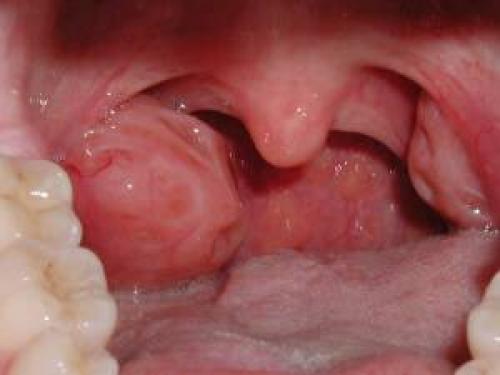

Если боль в горле не проходит неделю и дольше, речь может идти об ангине — тонзиллите, говоря иначе. Представляет собой воспаление миндалин (небных). Это наиболее частая причина длительного болевого синдрома.

Проявления следующие: жгучие, не проходящие ноющие боли в горле и ротоглотке в целом, экссудация интенсивного характера (выделяется гной в больших количествах), становление гнойных пробок (особых комковидных структур с резким гнилостным запахом), неприятные ощущения при дыхании, возможен отек тканей горла.

Это крайне опасное состояние, чреватое летальным исходом. Опухшие миндалины могут перекрыть просвет гортани, и больной попросту задохнется.

Также объективно выявляется гиперемированный зев, краснота объясняется воспалением, белый налет в глотке, обусловленный жизнедеятельностью флоры, рыхлая структура ротоглотки. Почти всегда наступает гипертермия — повышение температуры тела.

Тонзиллит — инфекционное воспаление миндалин, входящих в лимфоглоточное кольцо Пирогова. Это одна из самых распространенных причин сильной боли в горле при глотании, а также без него. Раздражителем может выступать еда, напитки, независимо от их температуры. Спровоцировать воспаление миндалин могут вирусы, бактерии, а также грибки.

Симптомами воспаления миндалин можно считать:

- отек и покраснение миндалин;

- появление пятен на миндалинах;

Тонзиллит

Нередко процесс охватывает только одну миндалину (суть патологии кроется в воспалении небных миндалин которых две). Потому так часто встречается неравномерный характер болевых ощущений.

Симптомы достаточно специфичны. Это односторонние боли в горле жгучего, тянущего характера, усиливаются при глотании, иррадиируют (отдают) в зубы, шею, челюсти. Так же характерна опухлость лимфоузлов на шее, нарушения дыхания по типу одышки или удушья.

Это опасное проявление, вполне способное закончиться отеком тканей глотки и асфиксией.

Также наблюдаются зуд в предверии мягкого нёба, повышение температуры тела, проблемы с общим состоянием. Объективно отмечается покраснение горла, рыхлость его структуры, налет с одной или обеих сторон.

● Тонзиллит — воспаление лимфатических желез (миндалин). Миндалины по бокам глотки краснеют, отекают, покрываются налетом.